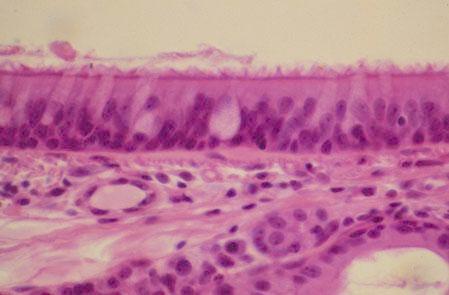

II-45 (5) Slide 73, Trachea (H&E). Examine aspects of the respiratory epithelium: cilia, basal body (dark line at cell apex), goblet cells, pseudostratified columnar cells and basement membrane.